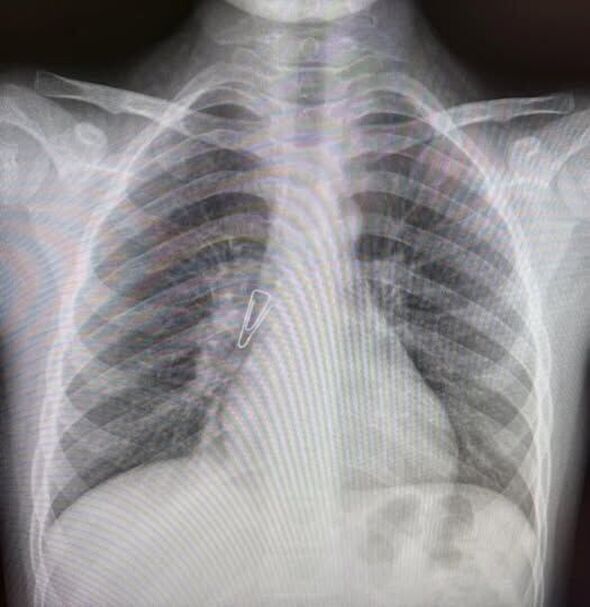

לפני כשנתיים, ילדה בת 9, בתו של שליח חב"ד באוקראינה, שאפה סיכת משרד. בסביבתה סברו תחילה כי היא בלעה אותה, ולא ראו סיבה לדאגה. עם זאת, לאחר שהילדה המשיכה לסבול משיעול במשך תקופה ממושכת, בוצע לאחרונה צילום חזה שחשף ממצא חריג: הסיכה הייתה תקועה בריאתה הימנית, מצב שעלול היה לגרום לנזק ריאתי משמעותי לטווח הארוך.

עם קבלת תוצאות הצילום, יצרה משפחתה של הילדה קשר עם ד"ר פטריק שטפלר, רופא בכיר במכון לרפואת ריאות במרכז שניידר לרפואת ילדים בפתח תקווה. ד"ר שטפלר הזמין את הילדה לטיפול, ובעקבות זאת הגיעה המשפחה לישראל.

לאחר הגעתה למרכז הרפואי, עברה הילדה פעולה מורכבת להוצאת הגוף הזר מדרכי האוויר. הפעולה התבצעה על ידי צוות רפואי משולב שכלל את ד"ר שטפלר וד"ר רועי הוד. במהלך ההליך, התגלו רקמת גרנולציה, סימני חלודה ודימום – עדויות לזמן הרב שבו שהתה הסיכה בתוך הריאה.

מאמץ הצוות הרפואי הוכתר בהצלחה, והסיכה הוצאה בשלמותה. בבדיקת ביקורת שנערכה כעבור שבועיים, נמצאו דרכי האוויר של הילדה נקיות לחלוטין, והיא במצב טוב. ממרכז שניידר נמסר כי הטיפול הוענק כחלק מפעילותו של בית החולים, שממשיך לספק טיפול מתקדם ומציל חיים לילדים מרחבי העולם גם בימים אלו, בהם המרכז פועל במתכונת חירום בצל המלחמה.